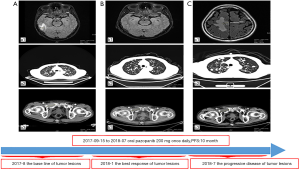

Given the evidence of the symptomatology, poor prognosis, and renal insufficiency (CKD4) for the patient, anti-tumor treatment was ruled out. Nevertheless, the patient was individually provided treatment with a reduced dose of oral pazopanib 200 mg once daily on September 10, 2017 as salvage therapy, and the symptoms of nausea, anorexia, and debilitation were improved in 2 weeks. Meanwhile, the level of the serum calcium dropped to a dangerously low level of 2.24 mmol/L. The creatinine and the creatinine clearance rate were 114 µmol/L and 49 mL/min at best response, respectively (Figure 3). Serial CT and magnetic resonance imaging (MRI) scans revealed evidence of objective disease response and subsequent disease stabilization for the focuses of the bilateral lung, the right pubis, and acetabulum (Figure 2). There was no recurrence of these symptoms, QOL improved, and PFS was 10 months. The treatment was well tolerated with minimal toxicity symptoms, such as leukotrichia and hypertension. Blood pressure (BP) ranged from 150–120/80–90 mmHg, which is classified as stage 2 hypertension (CTCAE 4.0). Neither rashes nor diarrhea was found in the patient.

Unfortunately, on July 25, 2018, we evaluated the progression of disease (PD), and pazopanib was discontinued due to the recurrence of anorexia and patient debilitation. The serum calcium was elevated to 3.59 mmol/L, while the creatinine reached 129 µmol/L (Figure 3). The CT scans confirmed that the focuses of the bilateral lung, the right pubis, and acetabulum progressed slowly. The cerebral metastases were obviously enlarged on MRI scan (Figure 2). Overall, the patient achieved progression-free survival (PFS) for 10 months. The timeline picture of the patient was shown in Figure 4.